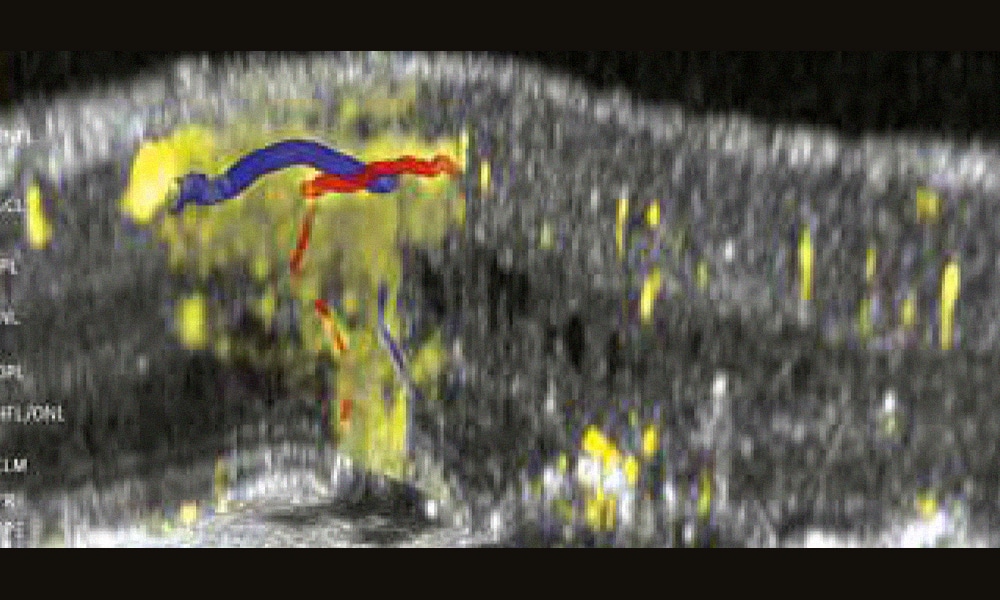

L’OCT-A est régulièrement utilisée pour le diagnostic des néovaisseaux maculaires et la surveillance des traitements par anti-VEGF de la dégénérescence maculaire liée à l’âge (DMLA) [2]. La précision des images et la suppression des artéfacts de projection dans les différents plans a même permis d’introduire de nouveaux concepts concernant les néovaisseaux maculaires de type 3 de la maladie [3]. L’utilisation de reconstructions en 3D est particulièrement importante pour la compréhension de la pathogénie de ces néovaisseaux de type 3. Ils prennent en effet leur origine dans le plexus capillaire profond et traversent verticalement les couches de la rétine. Ils peuvent donc apparaître raccourcis dans une vue bidimensionnelle [3]. La suppression des artéfacts de projection en mode 3D constitue une étape indispensable pour une meilleure analyse volumétrique de ce type de néovascularisation.

Dans cet article publié en avril dans JAMA Ophthalmology, les auteurs ont réalisé des comparaisons entre les images d’OCT-A et des coupes histologiques chez une patiente de 90 ans qui avait présenté des néovaisseaux maculaires de type 3 bilatéraux. La patiente a été suivie entre 2014 et 2019. Elle a bénéficié d’une imagerie multimodale (HRA Spectralis, Heidelberg Engineering) comportant des OCT-A et une angiographie à la fluorescéine. Les artéfacts de projection de l’OCT-A ont été supprimés avec un logiciel spécifique (SPX 1701 ; Heidelberg Engineering) qui réalisait une estimation tridimensionnelle de la forme des vaisseaux et comportait un filtre flou gaussien.[...]